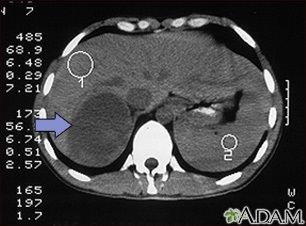

CT scan of the upper abdomen in a person with a right adrenal mass. The adrenal glands are located above the kidneys.